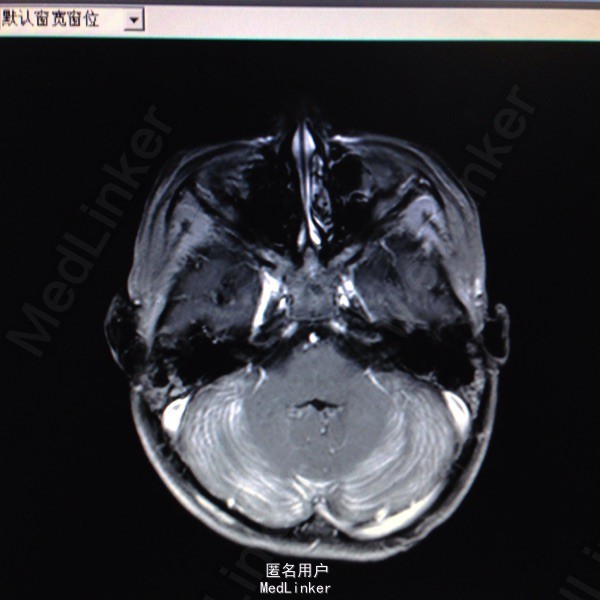

查体:面罩吸氧,甚至浅昏迷,CRT 2s,双侧瞳孔等大等圆,直径约4mm,对光反射迟钝,口唇红润,双肺可闻及干啰音,四肢肌张力偏高,以左侧为主,病理反射Babinski征阳性。辅查:血气分析提示碳氧血红蛋白8.4%,急诊行高压氧治疗,血常规:白细胞14.48G/L,血红蛋白120g/L,血小板291G/L;头颅MR检查:1.双侧小脑半球皮层及皮层下多发脑回样强化,双侧基底节区斑片状强化,结合病史资料,考虑一氧化碳中毒引起;2.双侧乳突炎症。

一氧化碳中毒脑病时多损伤基底节区、额叶、颞叶,本病例除基底节区损伤外,双侧小脑半球皮层及皮层下也受累,临床上还是比较少见的。